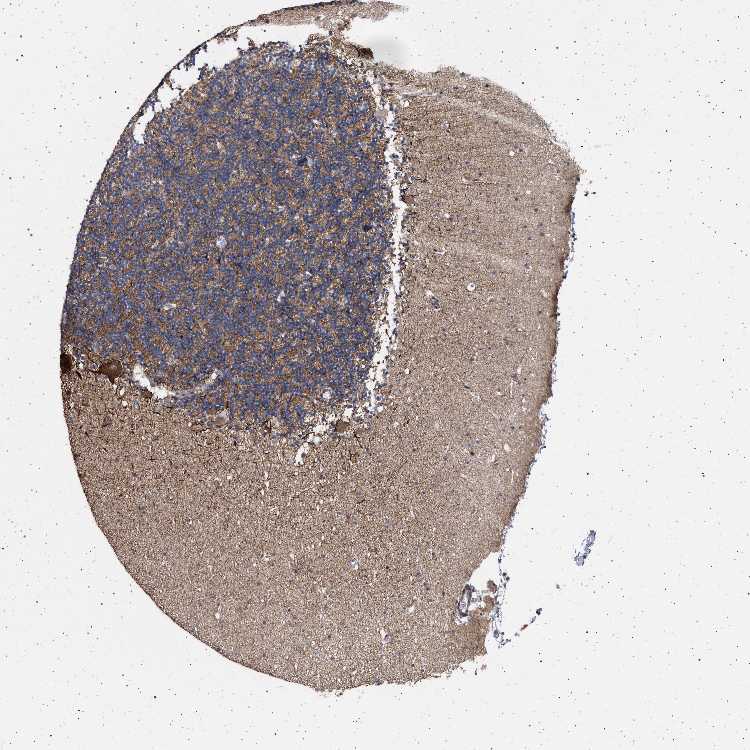

CEREBELLUM - Antibody stainingi

Antibody staining in the annotated cell types in the current human tissue is reported as not detected, low, medium, or high, based on conventional immunohistochemistry profiling in selected tissues. This score is based on the combination of the staining intensity and fraction of stained cells.

Each image is clickable and will lead to virtual microscopy that enables deeper exploration of all samples and also displays staining intensity scores, fraction scores and subcellular localization as well as patient and tissue information for each sample.

Antibody HPA021777Antibody HPA025306

Purkinje cells HighHigh

Cells in granular layer MediumLow

Cells in molecular layer LowMedium